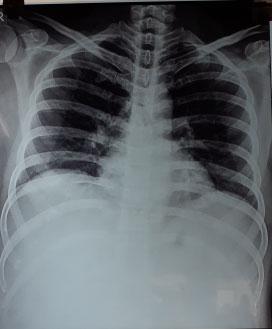

Tests to exclude other systemic diseases: Complete Hemogram, Blood Sugar, Urea, Creatinine, Chest X-ray, ECG, ANA in some cases.

We are in the middle of an unprecedented global pandemic. CORONAVIRUS 2019 (COVID-19), caused by severe acute respiratory syndrome CORONAVIRUS 2 (SARS-CoV-2 virus) has caused overlap in initial presentation with Acute Coronary Syndrome (ACS)1. Furthermore, symptoms alone are unhelpful, as quite a few screened for COVID-19 test negative and majority of COVID-19 infections are asymptomatic. There are multiple studies in the past which has shown that minimizing delays in reperfusion in patients with ACS is associated with improved outcomes2. Timely primary percutaneus coronary intervention relies heavily on systems of care, and not just the primary operator. There are multiple steps which are time consuming as in the emergency room. Every patient is required to establish contact history, symptomatology, chest X-ray, etc, before transfer to the Cardiac Catheterization Laboratory (CCL). CCL